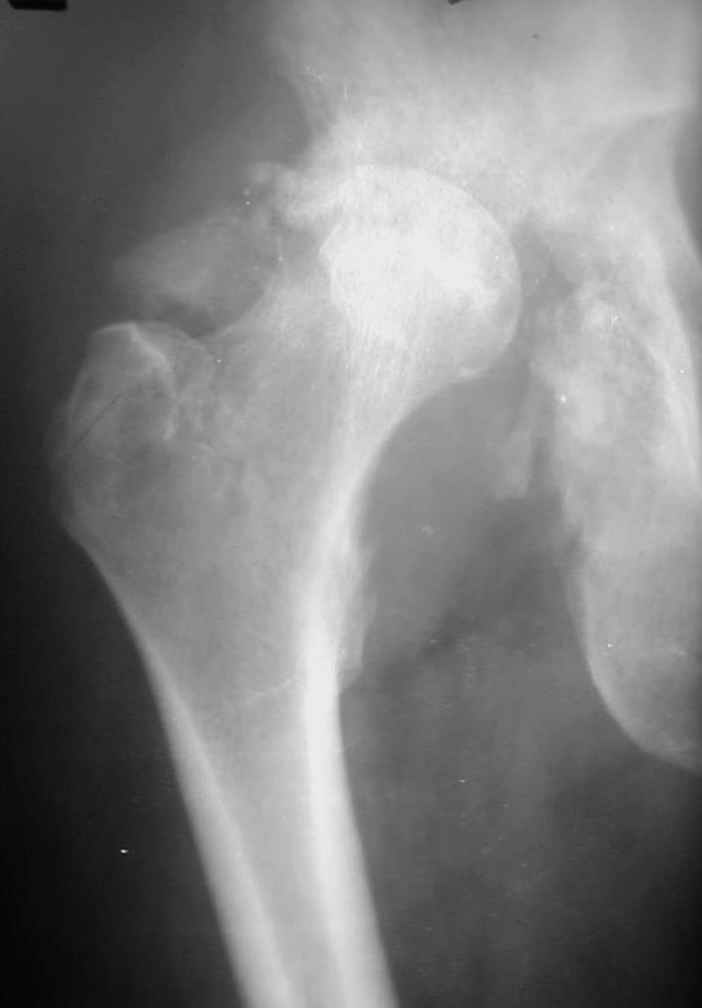

У Вас есть две возможности помочь этому пациенту. Либо выполнить артродез сустава, либо эндопротезирование. Артродез потребует достаточно много времени (примерно 6 иемяцев) и существенно ограничит его возможности. Эндопротезирование в данном случае - операция не из простых. Какие могут быть проблемы:

1.Большой костный посттравматический дефект вертлужной впадины. Поэтому необходима КТ для четкого планирования операции. При наличии контакта чашки с вертлужной впадиной на 55-60%% недопокрытие компенсируется за счет костной аутопластики собственной удаленной головкой (фиксация головки минимум 2-я винтами). Если недопокрытие большое, или не удается установить чашку, то можно установить кольцо Мюллера, опять же с костной пластикой.

В предлагаемой ситуации имеется последствия перелома задней колонны, что значительно больше усугубляет ситуацию, чем банальный дефект заднего края, и костного материала из головки может просто не хватить, тем более что в таком случае как раз вся нагрузка должна лечь на эту несчастную костную пластику. Наколько оправданы такие опасения, на Ваш взгляд?